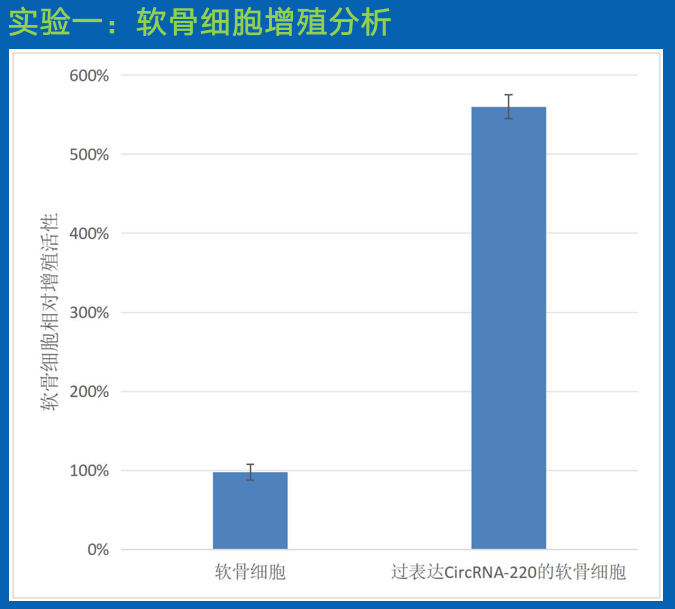

结论:

相比于空白对照而言,过表达 CircRNA-220 的软骨细胞的增殖能力明显得到改善。因此,可通过过表达 CircRNA-220 调控软骨细胞的增殖,来用于半月板和骨关节修复。